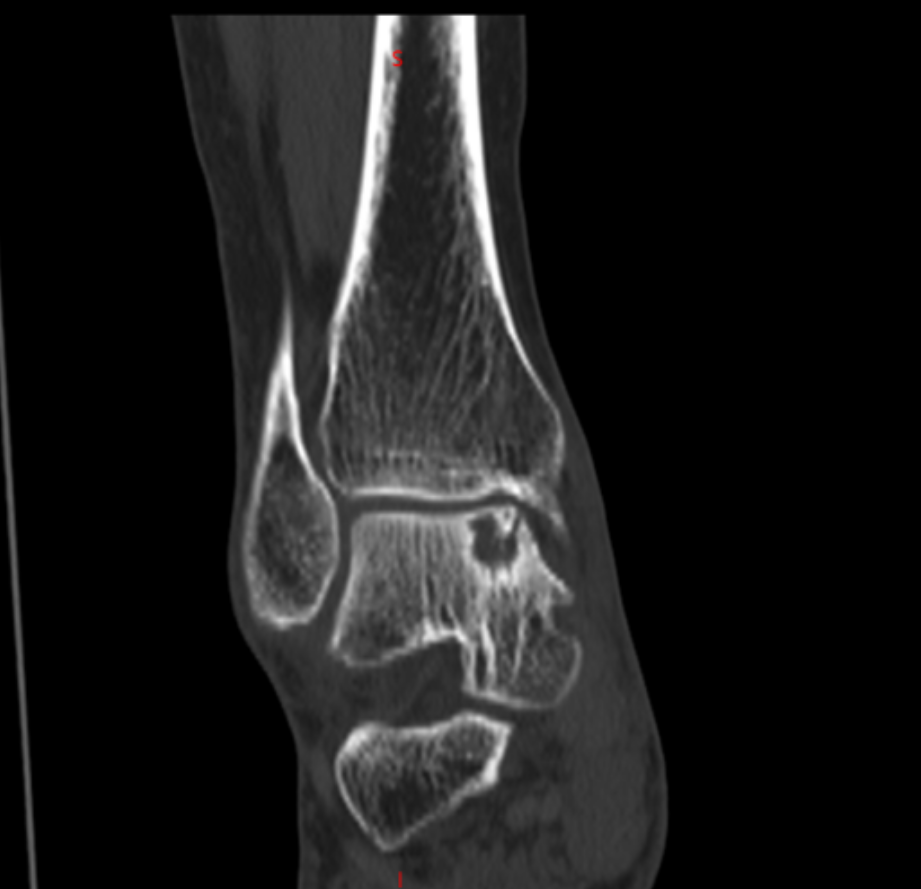

成人ai 、郑州大学附属郑州中心医院足踝外科李恒的诊室,李恒指着片子解释距骨内侧出现囊性变,这确实是棘手的问题。由于内部压力大,不但会疼痛,还有可能引起距骨塌陷骨折。我抢答:能不能不换踝关节?我还年轻,而且换踝关节费用太高了。

踝上截骨治疗踝关节关节病及距骨骨软骨损伤的手术治疗,对医生手术技术要求高,需要对踝足部的力线及平衡调整有丰富临床经验,术中要有很强应变能力。在李恒和足踝外科小组配合下顺利完成!

术后复查X线,非常完美。李恒提醒,踝关节是人体中负重最大的关节,出现问题会给生活带来极大的痛苦和不便,崴脚并非小事,若早期处理不当,错过最佳治疗时机,轻则遗留慢性疼痛,重则导致创伤性关节炎、慢性踝关节不稳等后遗症,所以“走路看路”+“积极的运动锻炼”,预防踝关节损伤非常重要!